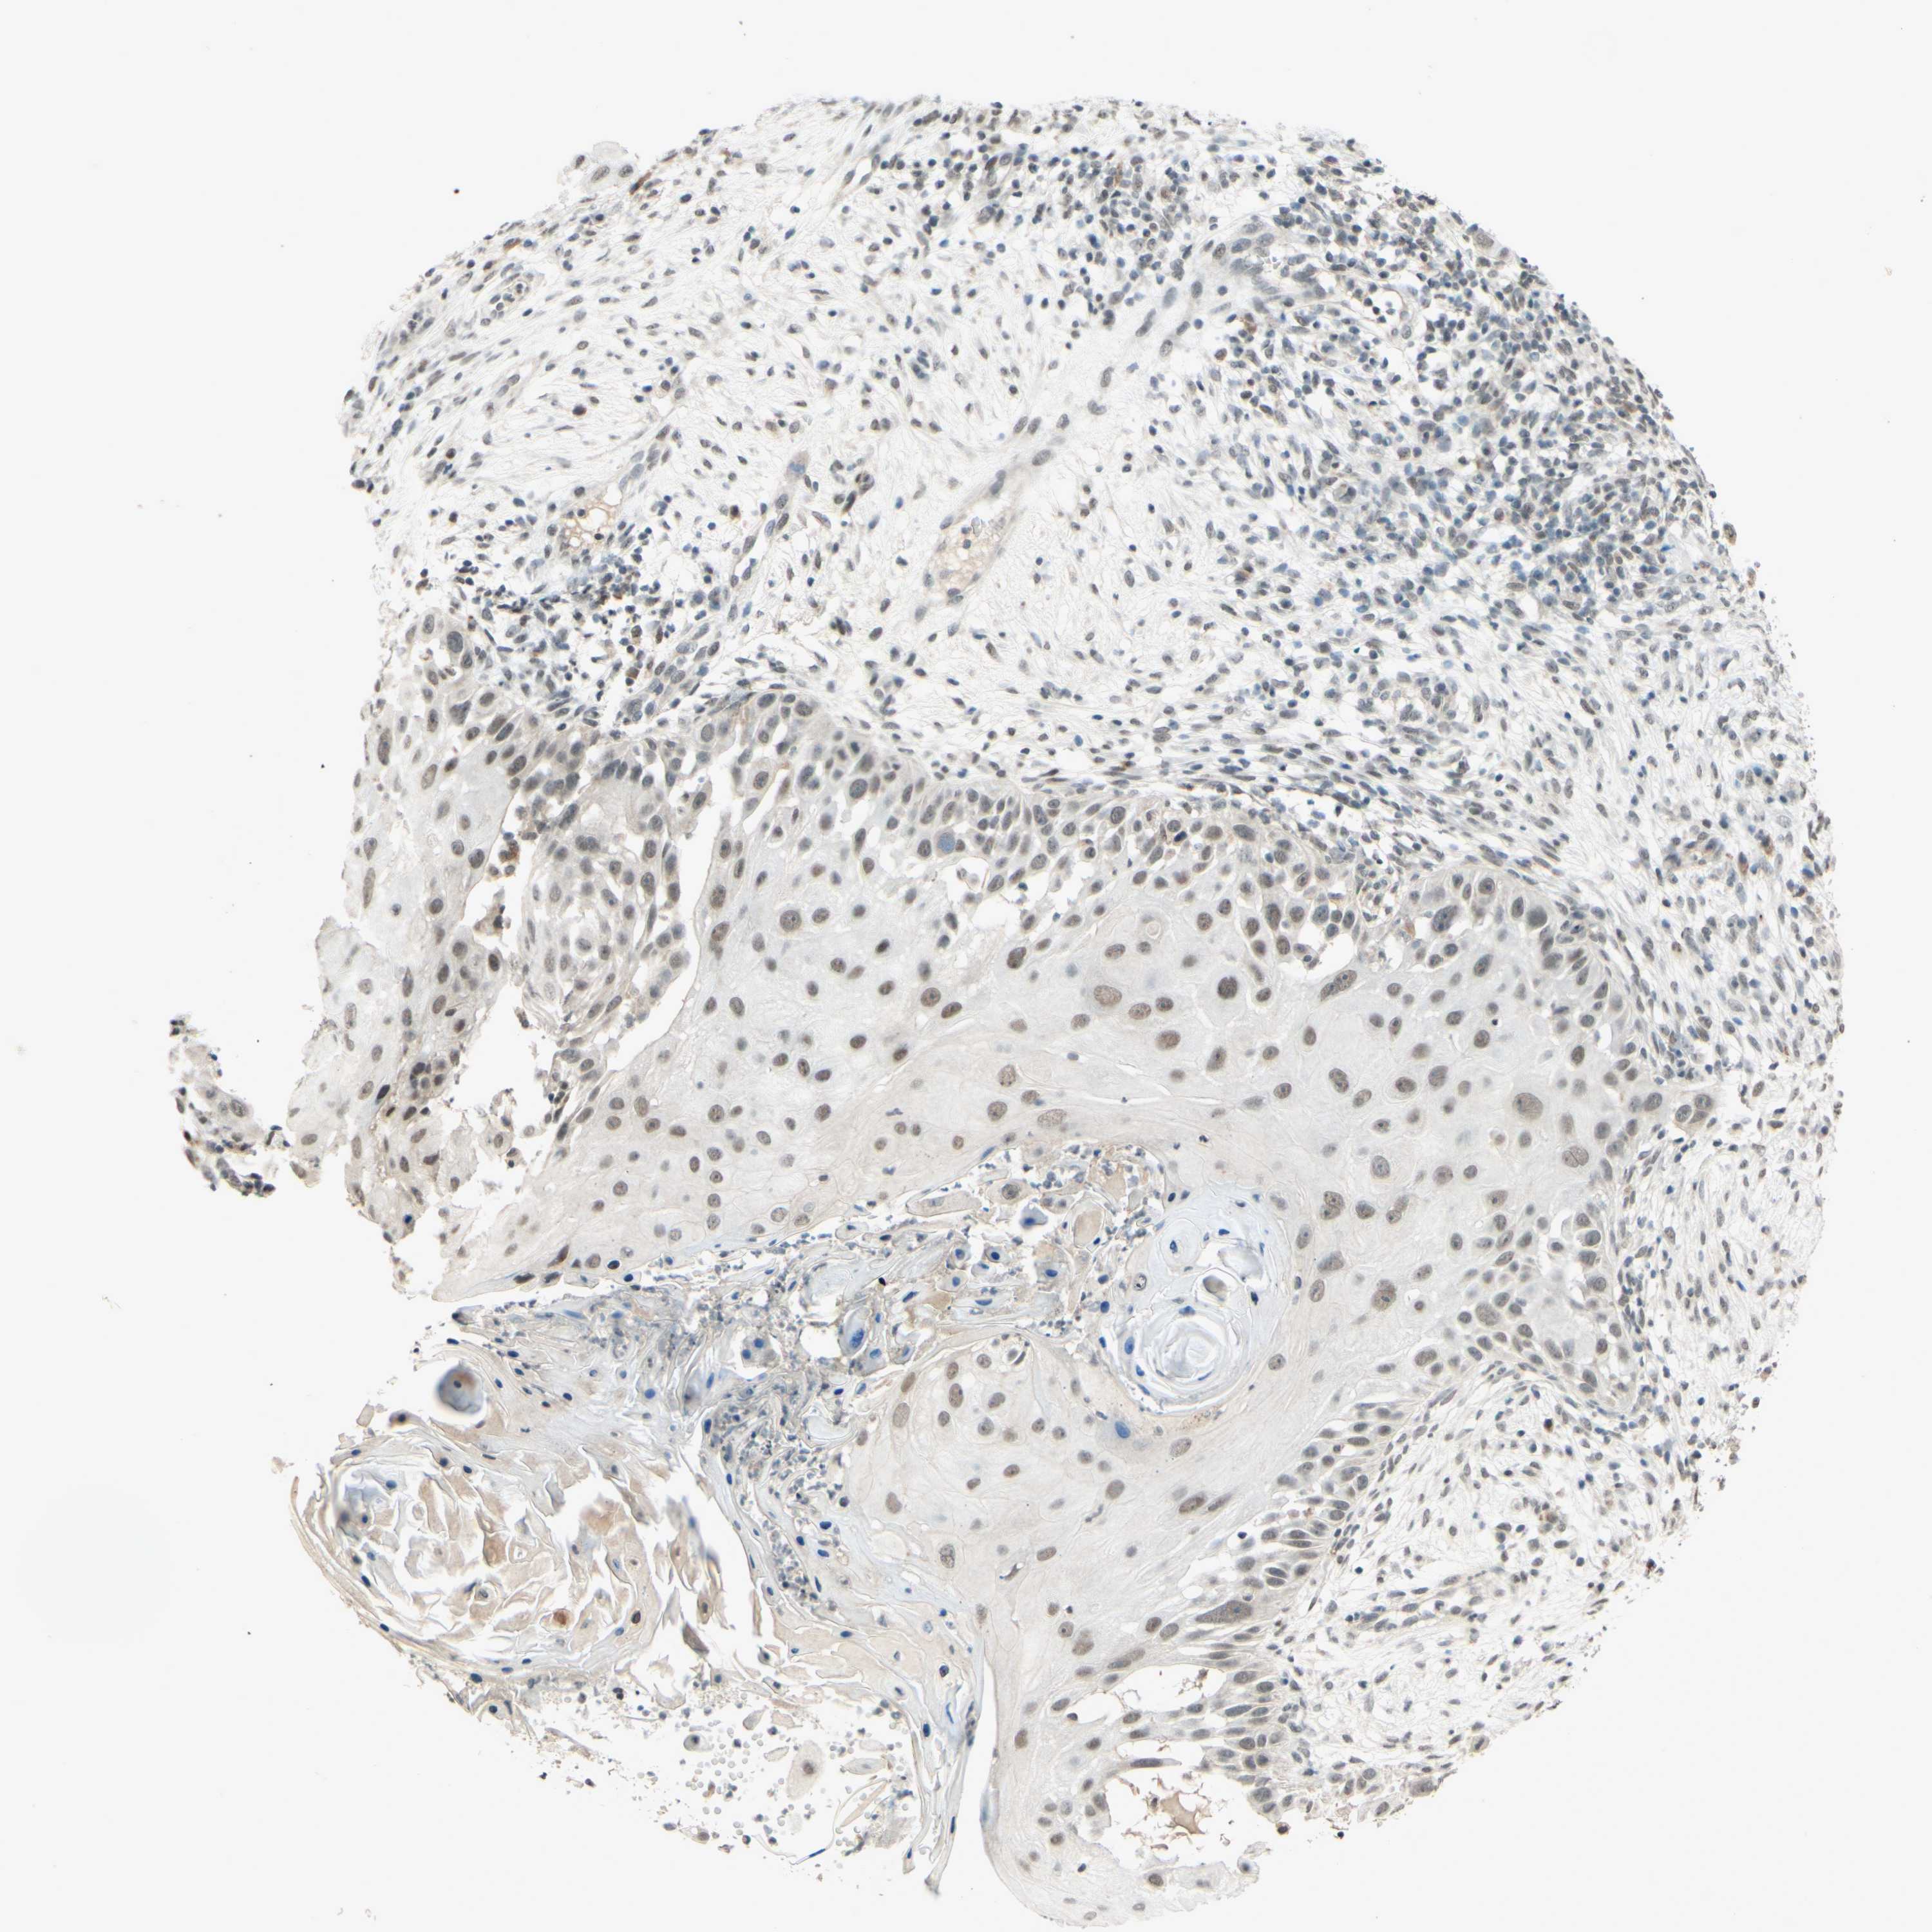

SKIN CANCER - Protein expressioni

A mouse-over function shows sample information and annotation data. Click on an image to view it in a full screen mode. Samples can be filtered based on level of antibody staining by selecting one or several of the following categories: high, medium, low and not detected. The assay and annotation is described here.

Antibody stainingi

Antibody staining in the annotated cell types in the current human tissue is reported as not detected, low, medium, or high, based on conventional immunohistochemistry profiling in selected tissues. This score is based on the combination of the staining intensity and fraction of stained cells.

Each image is clickable and will lead to virtual microscopy that enables deeper exploration of all samples and also displays staining intensity scores, fraction scores and subcellular localization as well as patient and tissue information for each sample.

Antibody HPA018248

Antibody HPA019127

Antibody CAB009196

Staining

High

Medium

Low

Not detected

Intensity

Strong

Moderate

Weak

Negative

Quantity

>75%

75%-25%

<25%

None

Location

Nuclear

Cytoplasmic/membranous

Cytoplasmic/membranous,nuclear

Squamous cell carcinoma in situ, NOS

Squamous cell carcinoma, NOS

Squamous cell carcinoma, metastatic, NOS

Basal cell carcinoma